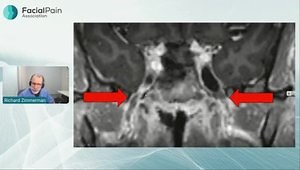

Decompression